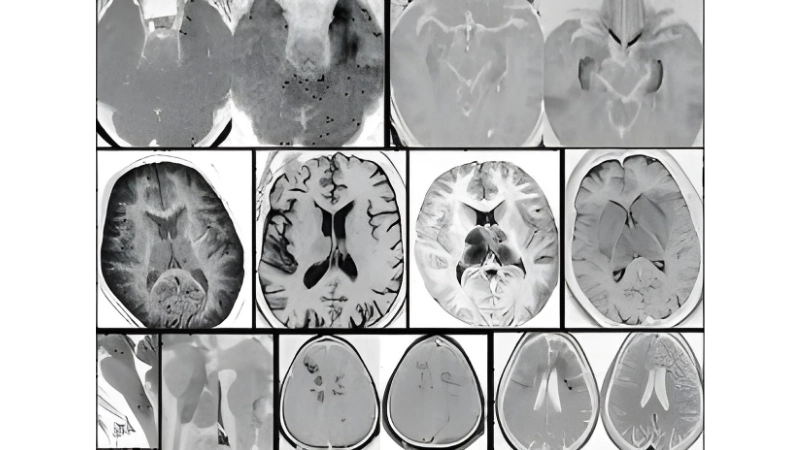

Image description of Murray Valley Encephalitis

Murray Valley Encephalitis is a rare but serious viral infection transmitted by mosquitoes, primarily affecting the brain and nervous system, with potential life-threatening complications.